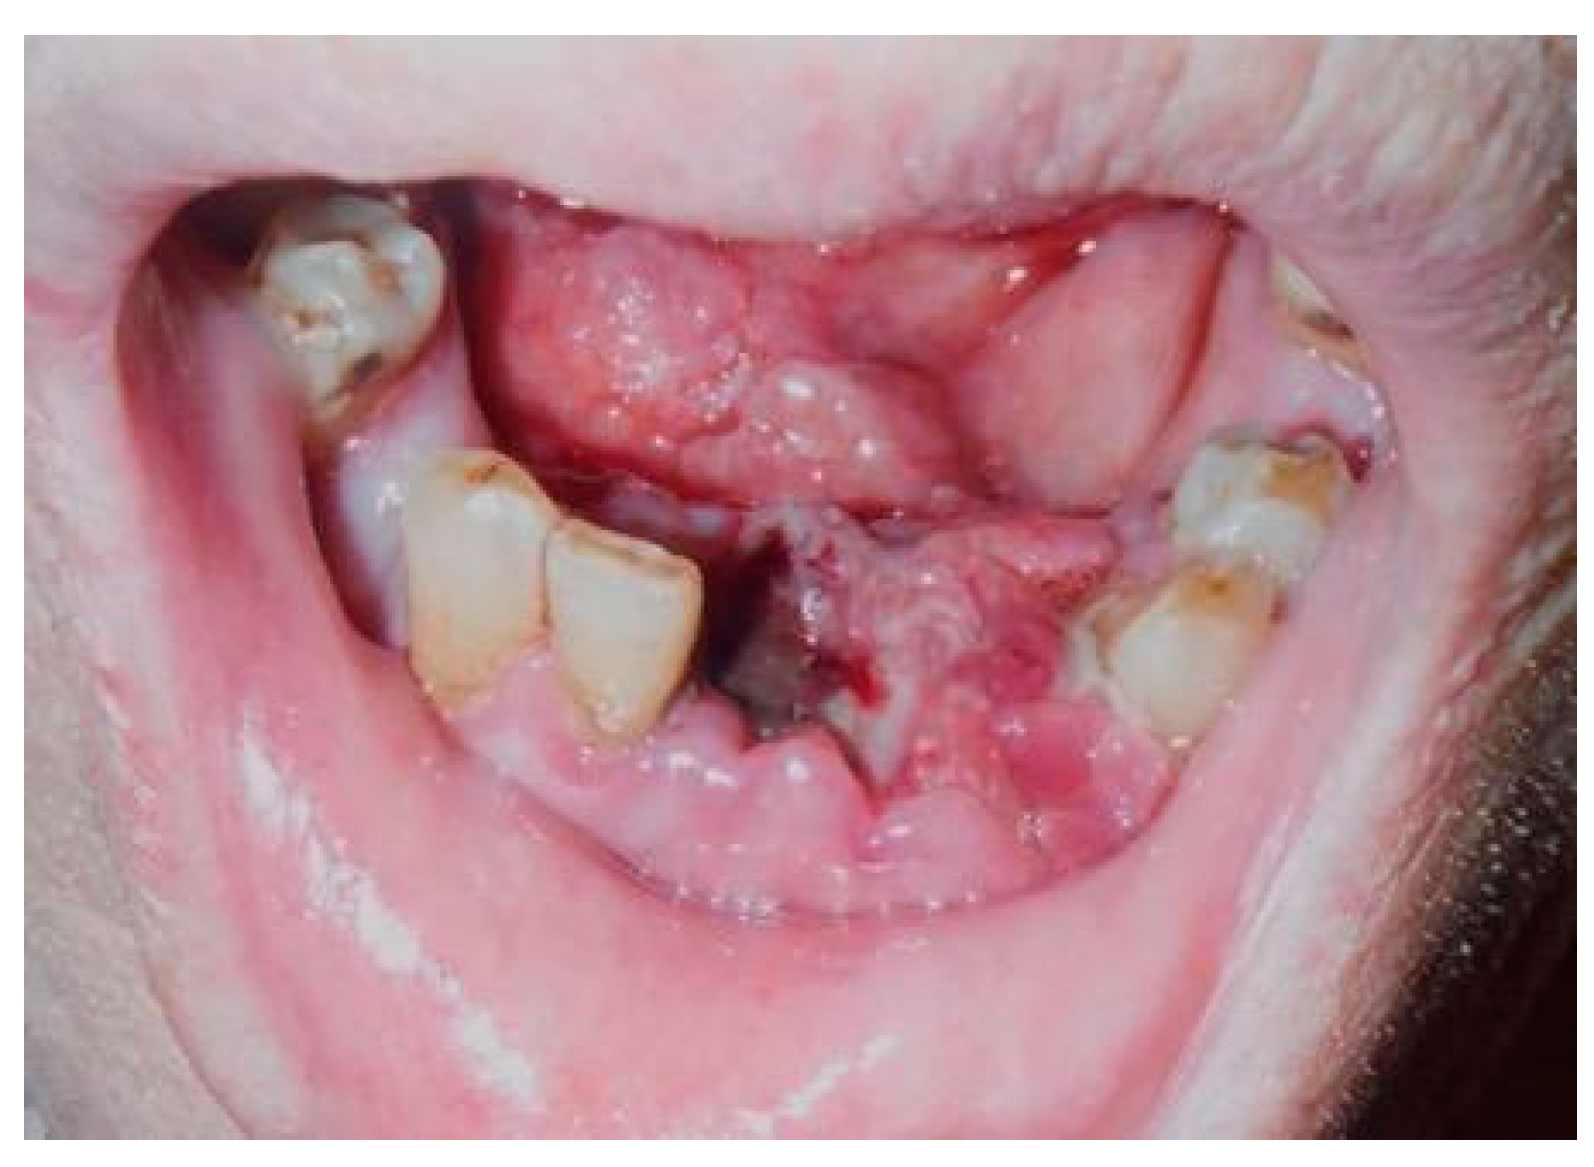

A 68-year-old Japanese man referred to the Department of Oral and Maxillofacial Surgery at the University Hospital of Tsukuba, complaining of a mass in the lower gingiva, one month after extraction of his frontal teeth. His medical history revealed diabetes mellitus, hypertension, hydrocephalus, and cerebral bleeding. He had no history of animal breeding. His general condition was good, and his face was symmetrical without trismus. The regional lymph nodes were not swollen. Intra-oral examination showed an irregular surface and an elastic hard mass with a necrotic ulcer between the right second premolar and the left first premolar, extending to the right floor of the mouth and measuring approximately 29 × 26 mm (Figure 1).

Figure 1.

Necrotic ulcer. Intra-oral examination shows an irregular surface and elastic hard mass with a necrotic ulcer, which measures approximately 29 × 26 mm.